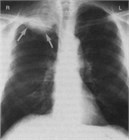

1. 肺がんの危険因子が多い患者では無症状でも胸部CTなど詳細な陰影の質的な評価と単純X線写真でとらえられないその他の異常所見の確認もする(推奨度1)

1. 肺がんの危険因子の乏しい患者での3cm以下の石灰化を伴う結節影は良性のことが多い(推奨度1)

1. 迅速に出現した結節影は円形肺炎を考える(推奨度1)